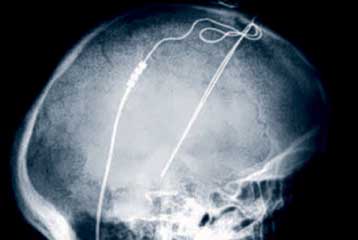

Αθήνα: Το Ειδικό Ιατρείο Επιληψιών και Μονάδα Καταγραφής Κρίσεων του Νευρολογικού Τμήματος του ΓΝΑ «Γ.Γεννηματάς» διοργανώνει στις 3 και 4 Απριλίου το 6ο Ετήσιο Εκπαιδευτικό Σεμινάριο για τις Επιληψίες, στο Ξενοδοχείο King's George, στο Σύνταγμα.